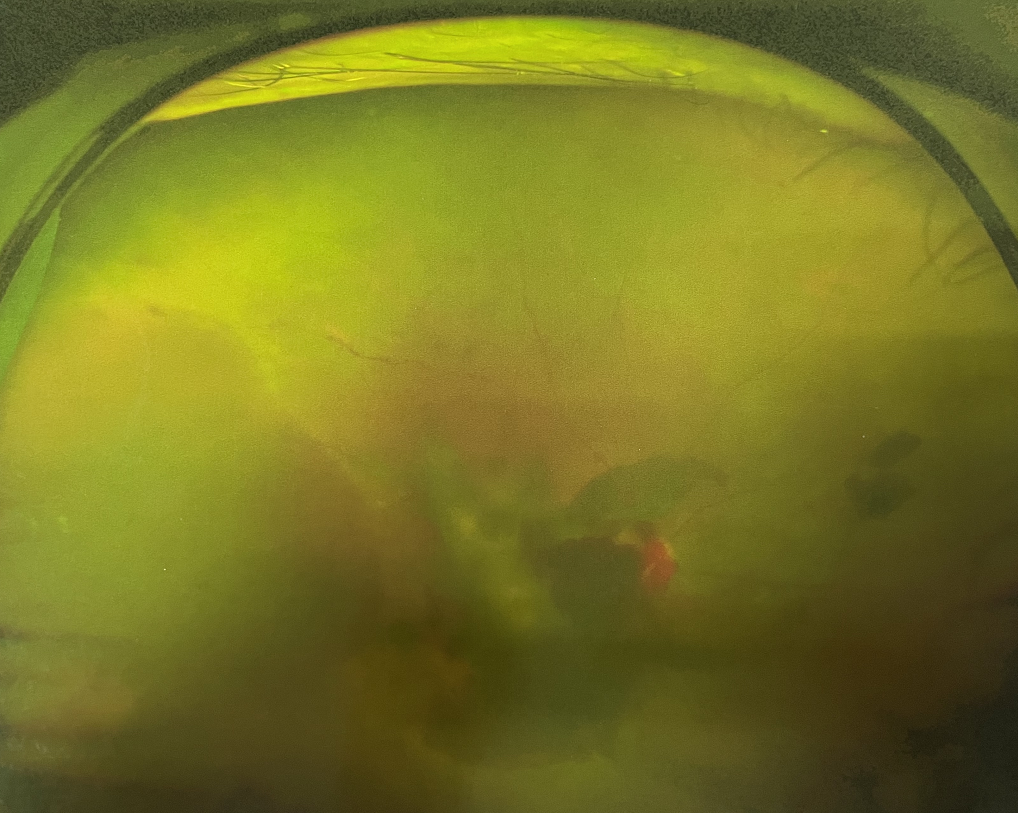

右眼術(shù)前

眼底病專科張小虎醫(yī)生檢查后,診斷王女士為“雙眼玻璃體積血、雙眼糖尿病視網(wǎng)膜病變V期”。(V期即5期,纖維增生期,出現(xiàn)纖維膜,可伴視網(wǎng)膜前出血或玻璃體出血。)

張小虎醫(yī)生為王女士進(jìn)行右眼玻璃體腔注藥術(shù),3天后進(jìn)行右眼23G玻璃體切割術(shù)后視力有所提升。

4個月后王女士來院取硅油,取油后視力恢復(fù)到0.6。“當(dāng)時來的時候真的只能看到模糊的影子,特別害怕覺得完了,想說眼睛估計要瞎了,沒想到手術(shù)后視力竟然提升了,現(xiàn)在也看得比較清楚了。”王女士說到。

張小虎醫(yī)生表示,糖網(wǎng)病進(jìn)展到嚴(yán)重增殖期帶來的視力損傷往往是極其嚴(yán)重的,目前王女士右眼從術(shù)前0.02恢復(fù)到術(shù)后0.6,已屬十分難得。